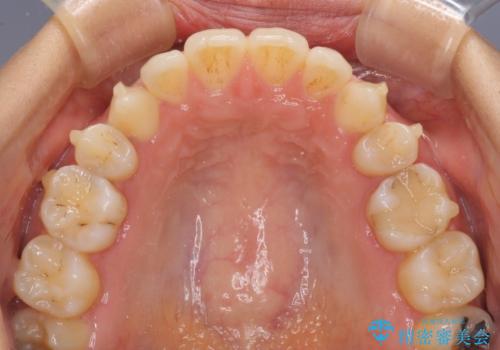

- 以前の矯正治療の後戻りにより、上の前歯にスペースができたことを気にして来院された患者様です。

インビザラインを用いて前歯のスペースを閉じつつ、上下の咬み合わせを構築していくこととしました。